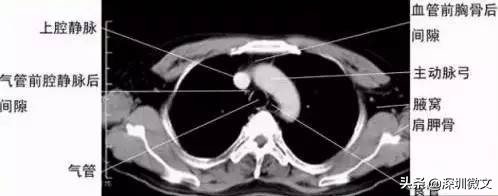

【CT:扫描更具立体感,分辨率更高】

CT正是在这样的医学背景下被研发。CT根本的检查和成像原理与X光相同,但二者最根本的区别在于,X光是将人体的一个或者多个器官投射到同一个平面上进行成像;CT是将人体的一个器官或者多个器官进行一层一层的扫描。

要解释这一点首先还是让我们从“CT”这个名称入手。“CT”的中文全称为“电子计算机断层扫描”。这个所谓的“断层扫描”可以这样理解,在人体的患病部位截取一个长方体,然后再把这个长方体依据不同的层厚与层距分为若干个小长方体进行分别扫描。

这项技术相比X光的突破在哪里呢?X光把前后重叠的肌肉、骨骼、器官全部投射到同一个平面上成像,这就涉及到相互遮挡等问题。这就像你要看一个人的背影,可只有一张正面的照片一样。所以X光的拍摄当中,有患者经常碰到医生要求从不同角度拍摄。

从X光到CT的突破和进步,我们可以广义的理解为:医生从一个长方形到从一个长方体看病变区域的突破。

除了维度的差别之外,CT另一个重要的进步和突破,在于对病变区域分辨率的差别。举例说明,人体相当的软组织对于X光的吸收量,与水对X光的吸收量很接近。成年人人体体重水占比高达70%,这样一来X光就很难在软组织和人体水分上最终呈现出“黑白色差”——软组织的病变就很容易被忽略。

由于CT的密度分辨率高,所以软组织、骨与关节都能显得很清楚。除了分辨率更高之外,CT机的又一项重大突破,是可以将各个部位对于X光吸收的差异直接量化。所谓的CT值就是对差异的量化,医生对于病变的判断因此更加准确。

医院里一般都是这个程序,X光没拍出来的,医生会建议再拍CT。最适于CT检查的病是脑部疾病,其中对肿瘤、出血及梗塞等病检查效果最好,其次是腹部实质脏器的占位病变,如肝、脾、胰、肾、前列腺等部位的肿瘤,对乳腺、甲状腺等部位的肿块也能显示并做出诊断;再次则是对胸腔、肺、心腔内的肿块,脊柱、脊髓、盆腔、胆囊、子宫等部位的肿块检查。